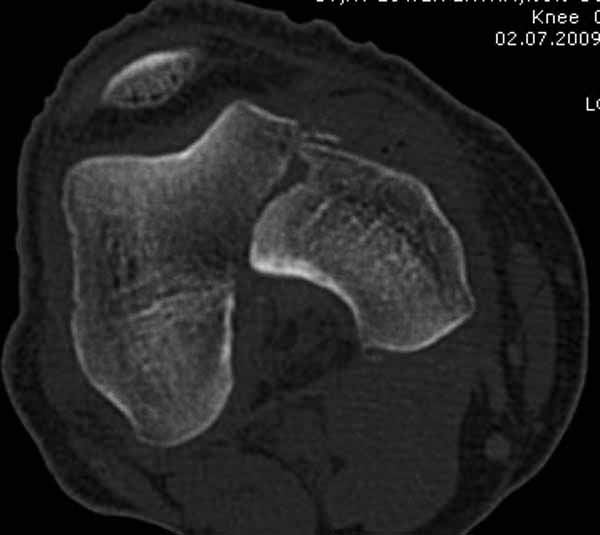

Остеосинтез, вестимо. КТ предварительно можно сделать, чтобы поточнее увидеть повреждения в межмыщелковой области. Перелом ближе к 33C1.

Представленный снимок не дает полную информацию. Там вроде простой перелом, но на самом деле, кроме смещенного (латерального, возможно медиального?) мыщелка на второй проекции имеется медиальный короткий дистальный фрагмент в флексии. Надо было сделать прямой снимок с захватом малоберцовой, который ориентировал бы стороны. Без КТ обычный снимок в дистракции поможет разобраться в топографии фрагментов.

Кстати, из вашего снимка, если отмечены вашим рентгенологом правильно, тогда получается снимок левого колена, и, соответственно, длинный переходящий в диафиз мыщелковый фрагмент находится медиально. Если так, тогда меняется сценарий фиксации!!!

И не обратите, коллега, пока не сделаете четкие анфасные снимки (лучше с дистракцией) где будет четко визуализироваться малоберцовая кость. Думается, что и КТ здесь будет уместно, дабы не пропустить возможное флексионное повреждение (перелом Hoffa).